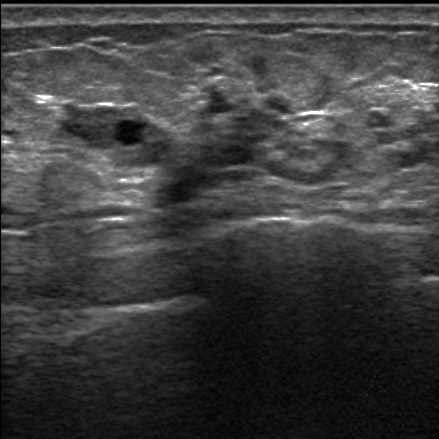

VAB超音波写真

乳腺診療には超音波検査が重要です。しこり、痛みなど乳腺の異常がある場合には診察と乳腺超音波検査を行い、実際にしこり(腫瘍など)があるかどうかを判断します。当クリニックでは富士フイルムヘルスケア社の超音波診断装置を使用しており、高周波プローブによって乳腺の繊細な画像検査が可能です。またリアルタイムエラストグラフィという機能でしこりの硬さを推定することができ、より正確な診断に役立ちます。

超音波検査で観察したしこりが乳がんを疑わず、良性疾患の可能性が高い場合には定期的な超音波検査による経過観察を行います。一方、しこりに悪性の可能性がある場合にはまず穿刺吸引細胞診(FNA:fine needle aspiration)を行います。これは注射に用いる針よりも細い針で乳腺のしこりなどから細胞を吸引し、顕微鏡で診断する検査です。この結果、悪性と判断されれば更なる精密検査を行い、乳がんに対する治療計画を立てていきます。FNAでも良悪性の判定が困難な場合や早期の乳がんが疑われ、ある一定量の組織採取が必要な場合には乳腺針生検を行います。当院ではより正確な診断をおこなうために、吸引をかけて組織を確保しながら針生検を行うVAB(vacuum-assisted breast biopsy)を行っています。FNAもVABも超音波検査で針の方向を確認しながら行います。